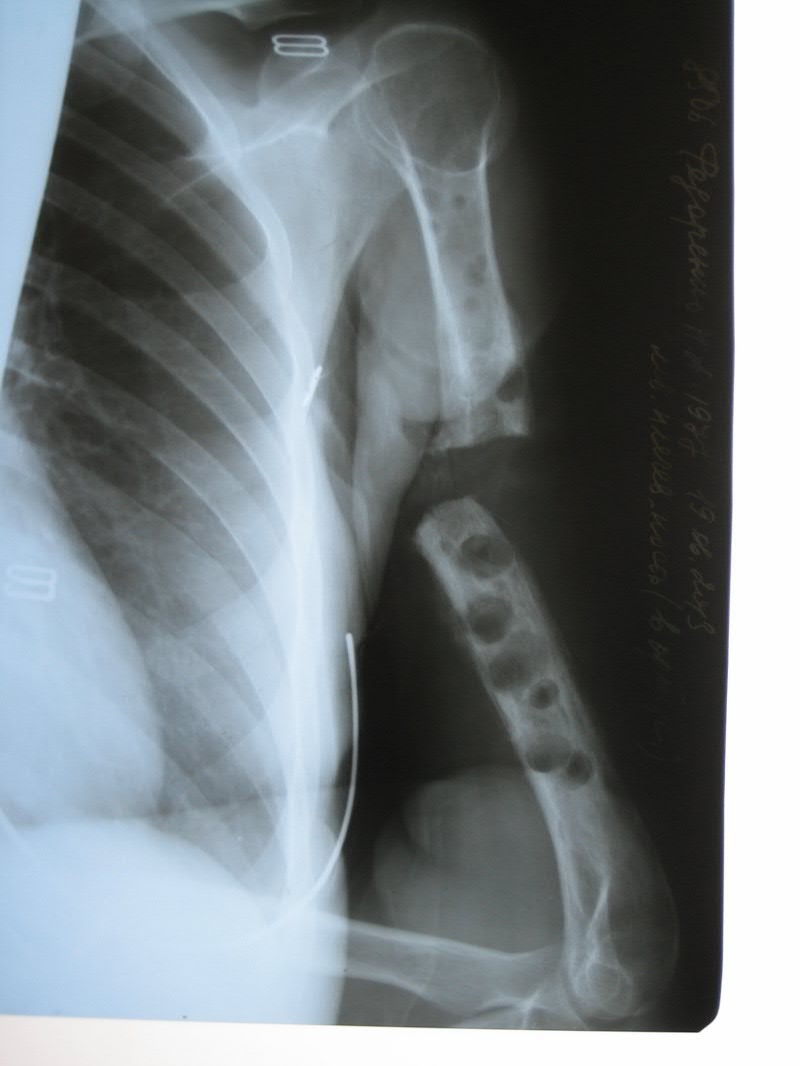

[Ortho] дефект-диастаз левой плечевой кости

п÷п╟я├п╦п╣п╫я┌п╨п╟ п╩п╣я┌ 40.

п■п╡п╟ пЁп╬п╢п╟ п╫п╟п╥п╟п╢ б═- п©п╣я─п╣п╩п╬п╪ п©п╩п╣я┤п╟.

п÷п╬я│п╩п╣п╢п╬п╡п╟я┌п╣п╩я▄п╫п╬ я│я┌п╟п╡п╦п╩п╦ я┌я─п╦ п©п╩п╟я│я┌п╦п╫я▀. п²п╟ п╡я│п╣ - п╬я┌я┌п╬я─п╤п╣п╫п╦п╣ п╪п╣я┌п╟п╩п╩п╟.

п║п╣п╧я┤п╟я│ - п╢п╣я└п╣п╨я┌-п╢п╦п╟я│я┌п╟п╥+я┐п╨п╬я─п╬я┤п╣п╫п╦п╣. п║я┐п╪п╪п╟я─п╫я▀п╧ п╢п╣я└п╣п╨я┌ п╬п╨п╬п╩п╬ 6 я│п╪. п■я▀я─п╨п╦ п╬я┌ п╡п╦п╫я┌п╬п╡. п≤п╫я└п╣п╨я├п╦п╦ п╫п╣я┌.